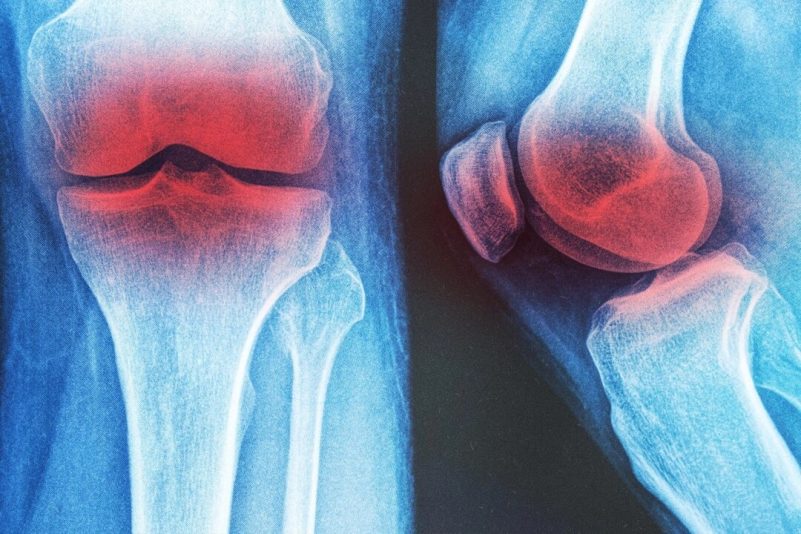

Trois thérapies non-médicamenteuses pour l’arthrose du genou

Environ 10 % des hommes et 13 % des femmes de plus de 60 ans souffrent d’arthrose du genou, une maladie associée à la douleur et à une perte de mobilité.